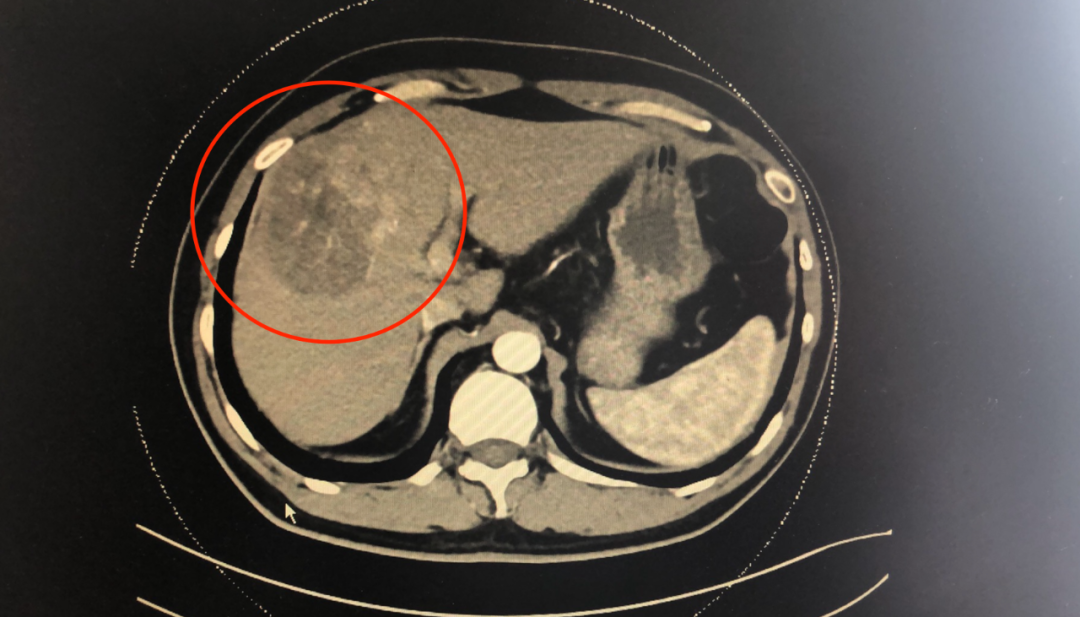

黄先生腹部疼痛2周不见好,在当地医院检查查出肝肿瘤,大小在8公分了